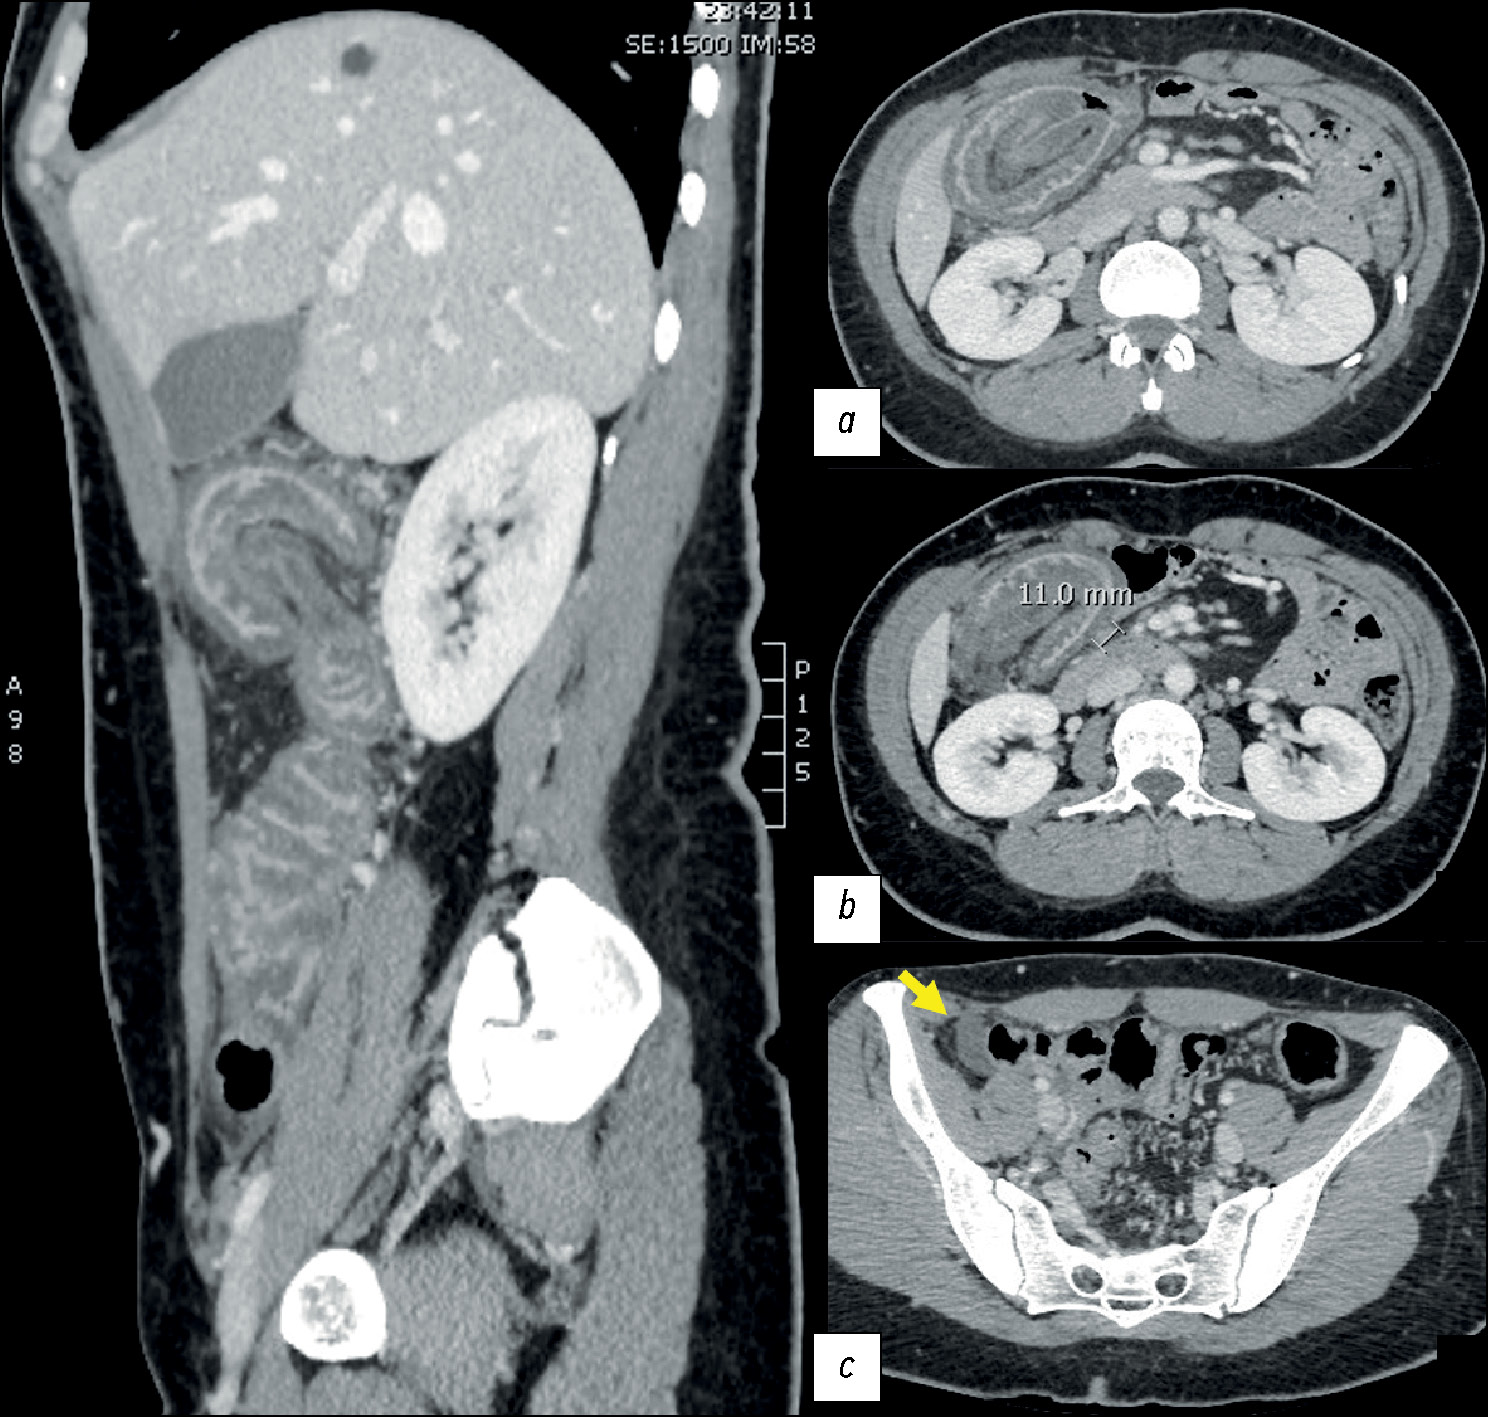

Idiopathic enterocolic intussusception: imaging findings in an abdominal emergency

Abstract

Adult intussusceptions are a rare cause of abdominal obstruction and are usually associated with a neoplastic disease; idiopathic forms are extremely rare. We report a case of enterocolic intussusception in a young woman who experienced symptoms of abdominal obstruction. Imaging findings were reported. On histological examination, no underlying diseases were found. The patient presented at the hospital for computed tomography because of persistent abdominal pain. Computed tomography revealed an enterocolic invagination involving the ileocecal valve and cecum and widespread edematous thickening of the colonic parietal walls.

Idiopathic enterocolic intussusception is an uncommon abdominal urgency in adults. Symptoms can be vague and persistent, delaying an accurate diagnosis. Imaging is crucial in these circumstances to make a diagnosis. Some computed tomography findings, such as a target-like bulk, may be suggestive.